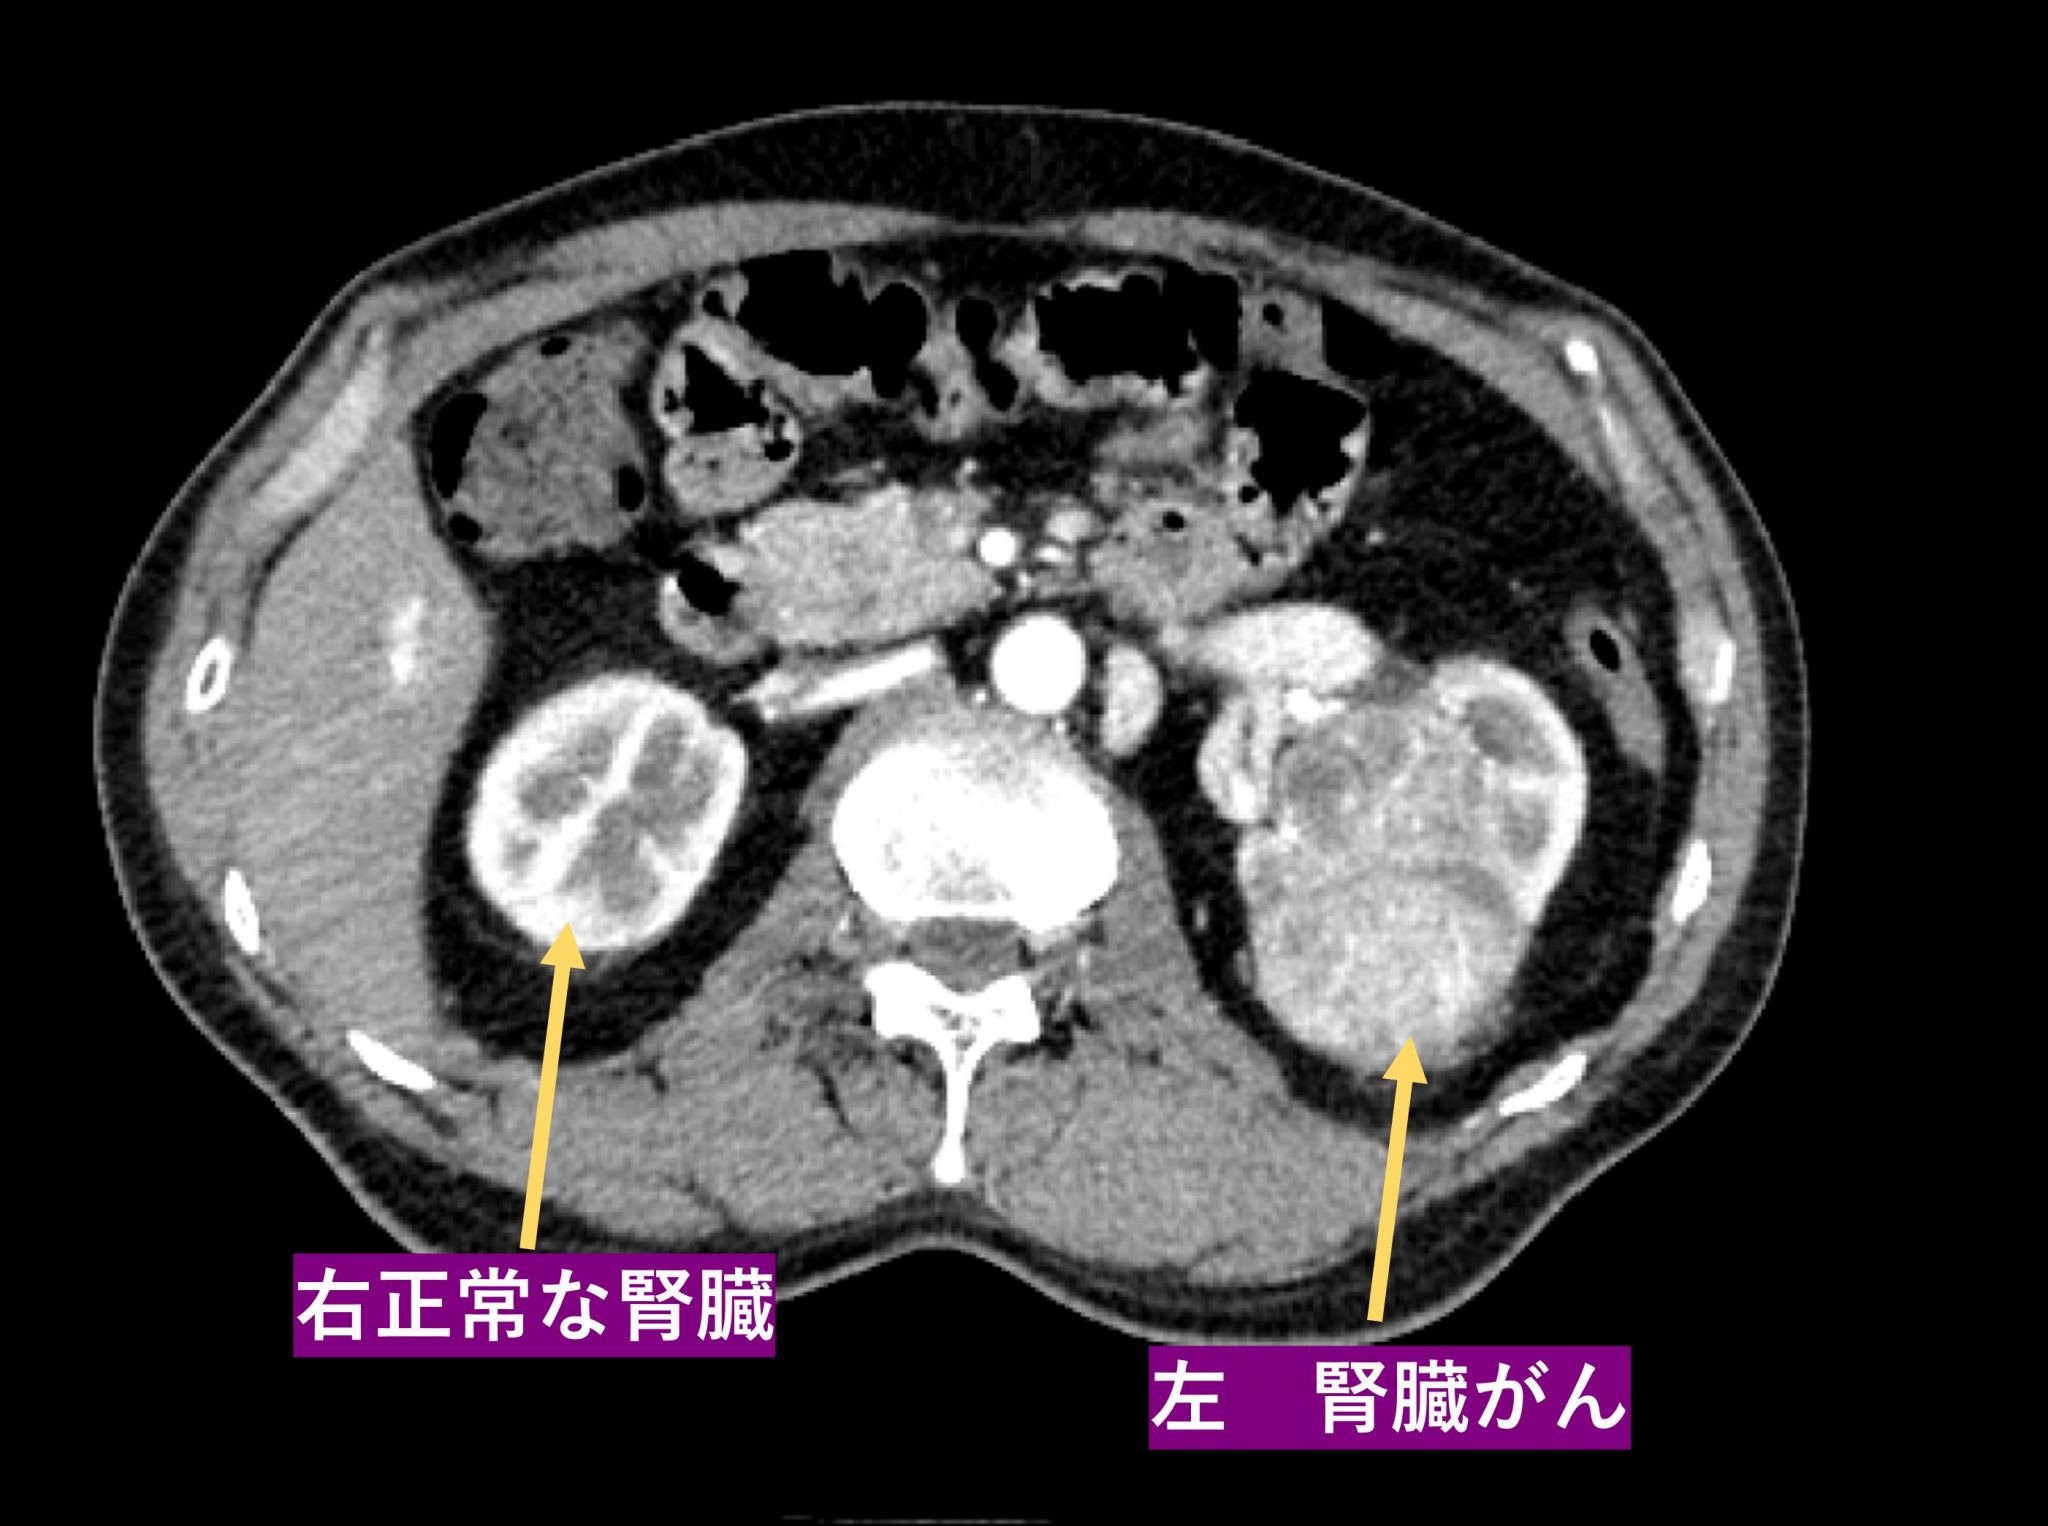

イメージング

画像検査は、腎細胞癌の診断と病期分類に役立ちます。

• MRIおよびCT スキャンは、腫瘍の位置とサイズを示すことができます。